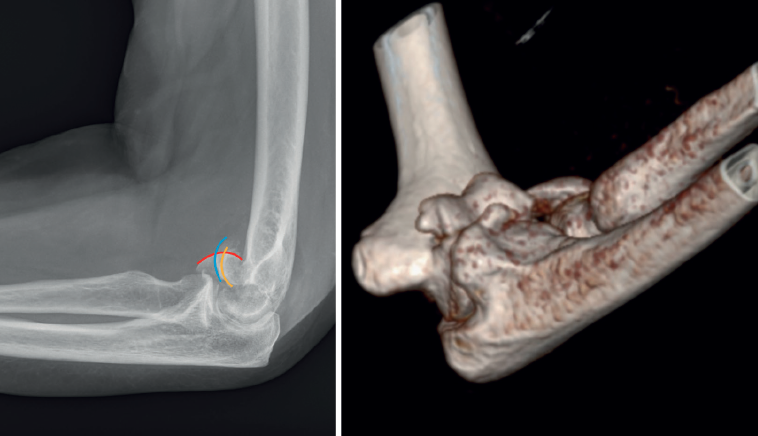

Para el diagnóstico, es fundamental la exploración física junto con pruebas de imagen. En algunos casos estas lesiones se asocian a luxaciones o subluxaciones de codo, por lo que es importante sospecharlas en estos pacientes. La clínica típica viene dada por edema, dolor e impotencia funcional, pero sin deformidad, y puede aparecer bloqueo a la flexoextensión del codo. Son imprescindibles radiografías en proyección anteroposterior y lateral del codo, donde es típico (aunque no siempre presente) el signo del doble o triple arco(2)(Figura 1). Al igual que en todas las fracturas articulares, es fundamental una TAC para confirmar el patrón de fractura y orientar el tratamiento.